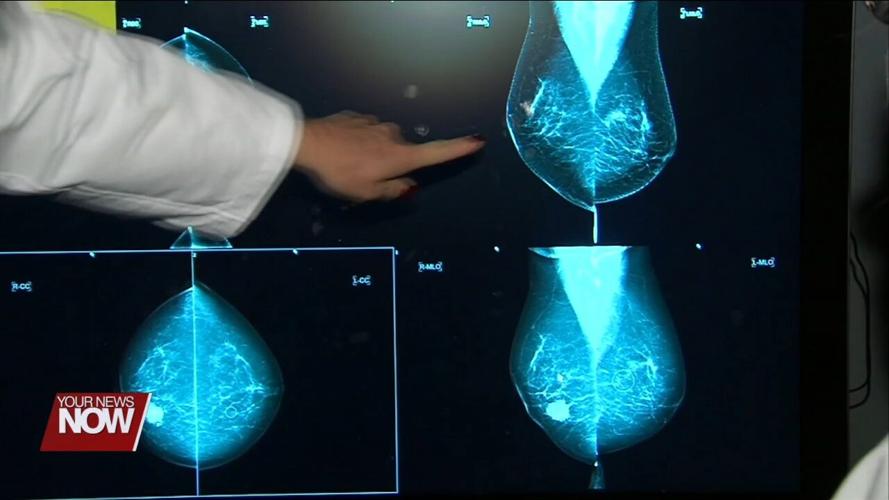

CLEVELAND, OH (CLEVELAND CLINIC) - The U.S. Preventive Services Task Force recently updated its guidelines for breast cancer screenings. Among the changes, women should now get mammograms every other year, starting at 40 instead of 50.

“Breast cancer experts have known and have widely agreed that the most lives from screening are saved when the screening begins at the age of 40. But even with that agreement, there has still been some variability in when to start screening, and when experts are recommending screening begin, and how frequently that screening should occur,” explained Laura Dean, MD, breast imaging radiologist with Cleveland Clinic. “I think the task force has really gone through the evidence and has, importantly, included that younger age group starting at age 40.”

Dr. Dean said that while 40 is the recommended age to start mammograms, some women may need to get them done even sooner. One reason could be if they have a family history of breast cancer.

The task force also addressed supplemental screenings, like MRIs and ultrasounds, for women with dense breast tissue.